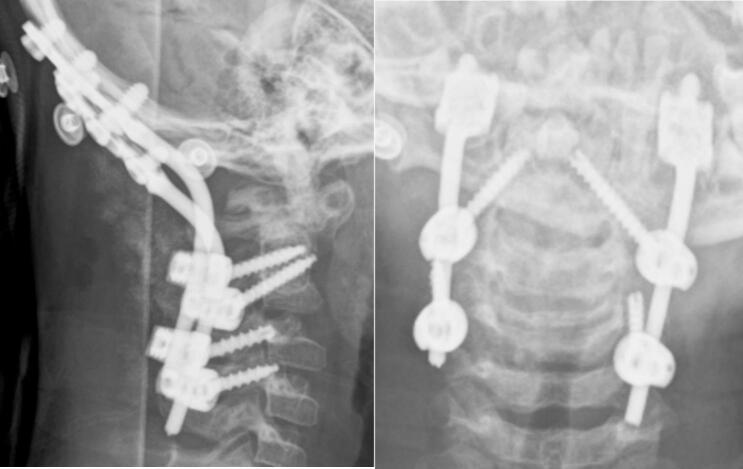

We present two cases of Os odontoideum accompanied by Down syndrome. Both patients were hospitalized due to progressive tetraparesis after falls several months prior. Upon examination, the patients exhibited myelopathy and were unable to walk or stand. MRI revealed spinal stenosis at the C1-C2 level due to atlantoaxial dislocation. C1-C2 fixation using Harms' technique was performed in both cases. One case experienced a complication involving instrument failure, necessitating revision surgery.

我们报告两例伴有唐氏综合征的齿突缺如病例。两名患者均因数月前跌倒后进行性四肢轻瘫入院。检查时,患者表现出脊髓病,无法行走或站立。MRI显示由于寰枢椎脱位,C1-C2水平存在椎管狭窄。两例均采用哈姆斯(Harms)技术进行C1-C2固定。其中一例出现器械故障并发症,需要进行翻修手术。